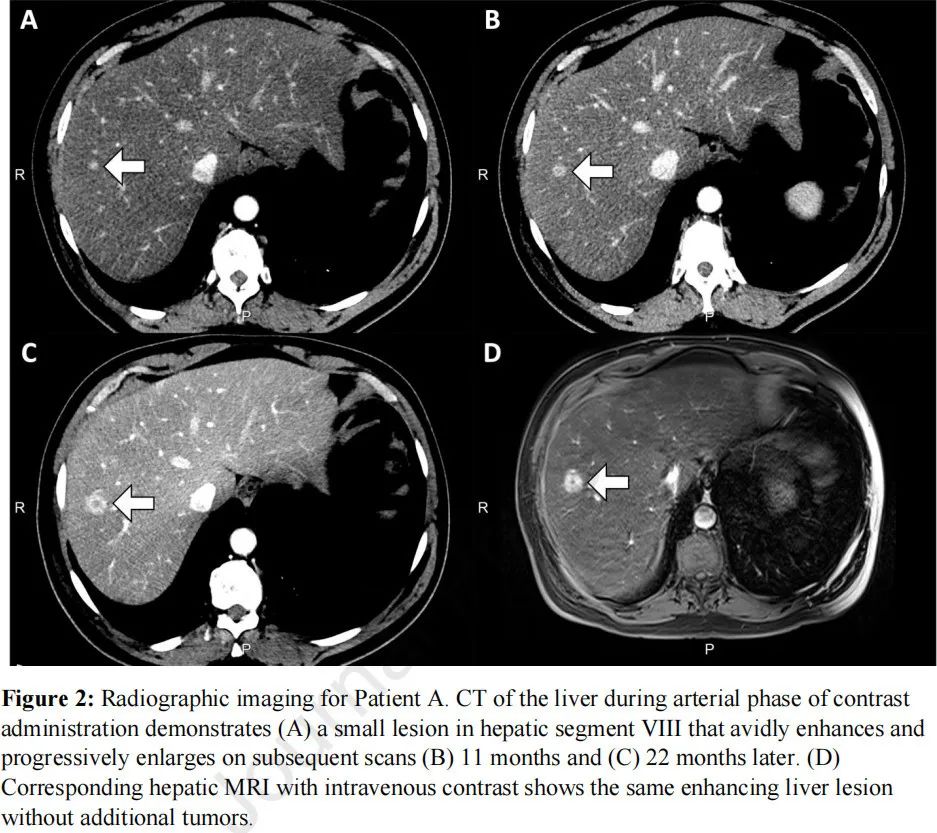

患者A为58岁的男性,2016年11月被诊断为IIIC期(cT4N2M0)肺鳞癌。患者有肝脂肪变性史,既往大量饮酒,吸烟史20包/年。血清HBV和HCV阴性。患者于2017年3月开始接受NSCLC治疗,采用卡铂和紫杉醇同步放化疗。然而,6个月后,活检显示右肺上叶局部复发(图1A)。该患者随后参加纳武利尤单抗、恩替司他和阿扎胞苷vs纳武利尤单抗单药治疗的临床试验,被分入单药治疗组,于2017年11月~2020年3月接受单药纳武利尤单抗治疗。患者因肝脏病变增大而退出试验。影像学回顾性检查发现,该肝脏病变自2018年5月以来一直存在,但病情稳定,疑似转移(图2A-D)。在纳武利尤单抗单药治疗期间,肺部肿瘤病情稳定。

图2